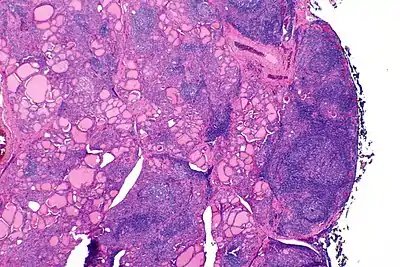

![]() | |

| The thyroid of someone with Hashimoto's thyroiditis as seen with a microscope at low magnification | |

Histologically, the hypersensitivity is seen as diffuse parenchymal infiltration by lymphocytes, particularly plasma B-cells, which can often be seen as secondary lymphoid follicles (germinal centers, not to be confused with the normally present colloid-filled follicles that constitute the thyroid). Atrophy of the colloid bodies is lined by Hürthle cells, cells with intensely eosinophilic, granular cytoplasm, a metaplasia from the normal cuboidal cells that constitute the lining of the thyroid follicles. Severe thyroid atrophy presents often with denser fibrotic bands of collagen that remains within the confines of the thyroid capsule.[41]